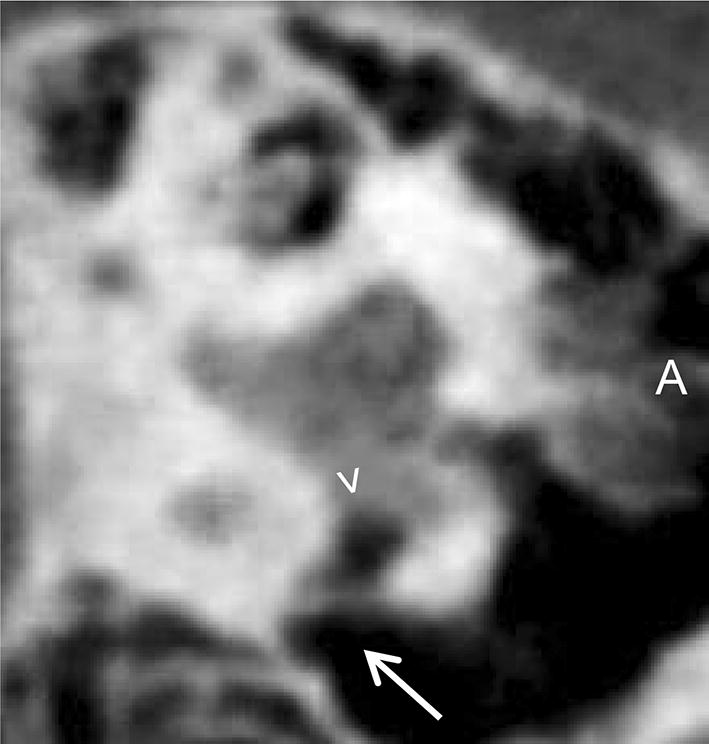

Bony overhangs at the RWN were clearly visualized in seven cases (26%, Fig. 3). Granulation tissue inside the RWN, not allowing to identify the round window membrane (RWM), was found in four cases (15%, Fig. 4a). In all other 23 cases (85%) the RWM was clearly visible. Additional soft tissue inside the oval window niche was seen in four cases (15%, Fig. 4b). In one case (4%) it was possible to describe an additional, secondary RWM (Fig. 5). Regarding these 108 radiologically ‘tiny’ items the neuro-radiologist was not able to make a clear decision in nine cases (8%).

Fig. 5

Sagittal view of a left temporal bone in CBCT imaging. The RWN ( >) can be clearly identified but seems capped by a secondary membrane ( →)